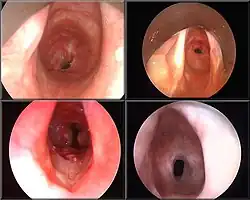

![]() Podgłośniowe zwężenie pointubacyjne na zdjęciu rentgenowskim |

Zwężenia krtaniowo-tchawicze (ang. laryngotracheal stenosis, LTS) – grupa chorób o różnej etiologii, cechujących się zaburzeniem drożności krtani i tchawicy. Zwężenia mogą przyjmować różną lokalizację, kształt i długość, a w zależności od miejsca i stopnia ograniczenia światła dróg oddechowych powodować różny stopień nasilenia duszności i zaburzeń głosu[1]. Najczęściej są wynikiem powikłań po intubacji i tracheotomii, przyczynami mogą być także urazy krtani i tchawicy o innej etiologii, refluks krtaniowo-gardłowy, nowotwory, wady wrodzone, infekcje i choroby układowe[2][3]. Rozpoznanie jest stawiane na podstawie wywiadu, spirometrii, laryngoskopii, wideostroboskopii, badań endoskopowych i obrazowych[2][4]. Wybór rodzaju leczenia jest zależny od przyczyny, umiejscowienia i stopnia zwężenia, najczęściej ma zastosowanie leczenie chirurgiczne, obejmujące endoskopowe poszerzanie mechaniczne lub laserowe, założenie stentu albo chirurgię otwartą (rozszczepienie chrząstki pierścieniowatej, laryngotracheoplastykę lub resekcję zwężenia). W zwężeniach ciężkiego stopnia, zagrażających życiu, konieczne bywa wykonanie tracheotomii[1][5][6].